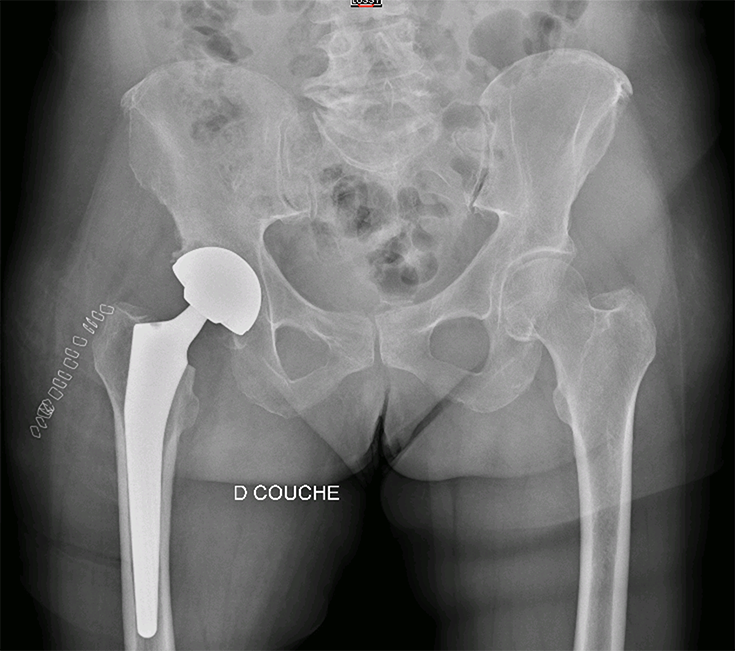

Radiographie bassin de face avec coxarthrose droite

- Dr Dumoulin